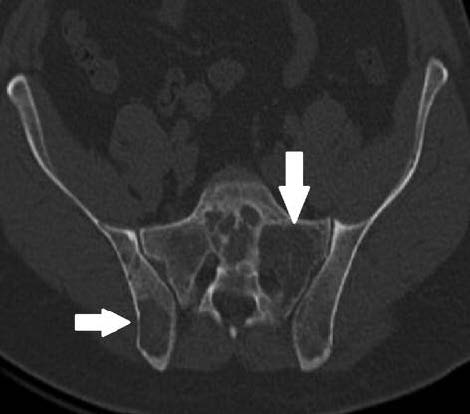

Рис. 2. Компьютерная томограмма костей таза (2012 г.): обширный очаг деструкции в левых боковых массах крестца.

При КТ грудного отдела позвоночника через 1,5 года отмечены увеличение размеров ранее дифференцируемых очагов деструкции и появление новых очагов. В 2012 г. проведено комплексное КТ-исследование грудной и брюшной полостей, а также области малого таза, где отмечалось многократное увеличение количества очагов деструкции во всех видимых в зоне сканирования костях, с формированием больших участков деструкции (в боковых массах крестца слева), частичным слиянием и увеличением размеров ранее существовавших очагов (рис. 2). Структура новых очагов аналогична старым – в толще большого количества очагов имелись костные фрагменты точечного и линейного вида. Диагностирован новый компрессионный перелом I грудного позвонка со вздутием и деструкцией его правого поперечного отростка и полудужки. В паравертебральных мягких тканях, слева от компримированного VIII грудного позвонка, сформировалось образование пониженной мягкотканой плотности с вкраплениями извести в его толще размером 32¥18¥27 мм; аналогичное образование визуализировалось в переднем отрезке II ребра справа в диаметре около 20 мм с интраторакальным распространением.